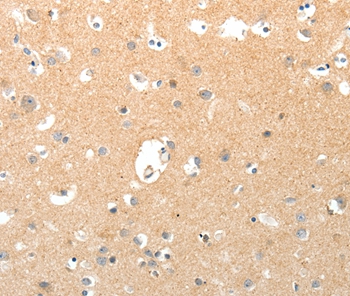

Immunohistochemical analysis of paraffin-embedded Human brain tissue using #37269 at dilution 1/40.